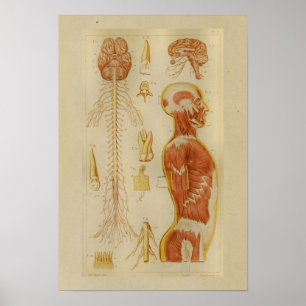

Impressão da anatomia dos músculos e dos nervos

Preço27,80 €